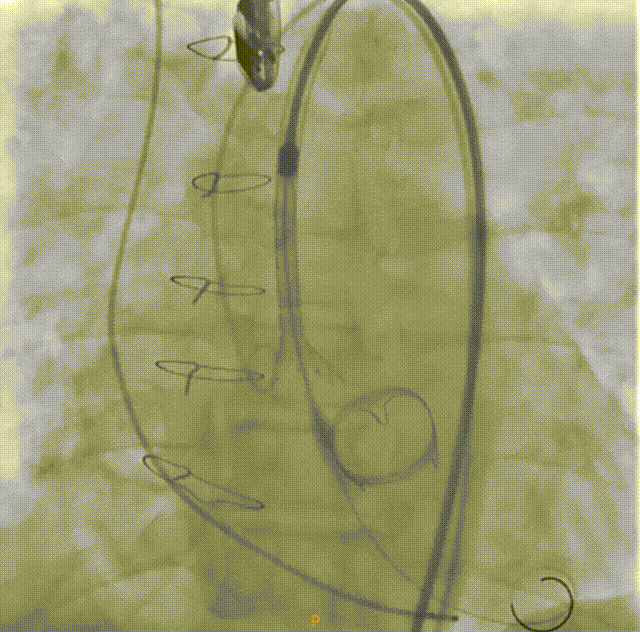

对于这样挑战的复杂病变,使用VenusA-Plus®可回收输送系统,为手术增加了一重保障,拟选择L29型号瓣膜经由右侧股动脉入路,选择标准位偏高2mm左右进行释放完成手术。瓣膜释放过程中,观察瓣膜位置,当瓣膜植入位置不合适,可以及时回收,重新调整位置再次释放,降低手术风险,提高手术成功率。

在放射科,超声科和麻醉科的通力协作下,顺利完成了术前准备,术者团队在术中谨慎建立轨道,根据主动脉根部造影的结果,初步判断释放体位是否合适观察瓣叶活动度、是否合并反流,选择合适的跨瓣体位。瓣膜释放前优先确认猪尾管位置,避免瓣膜在释放过程中脱载。